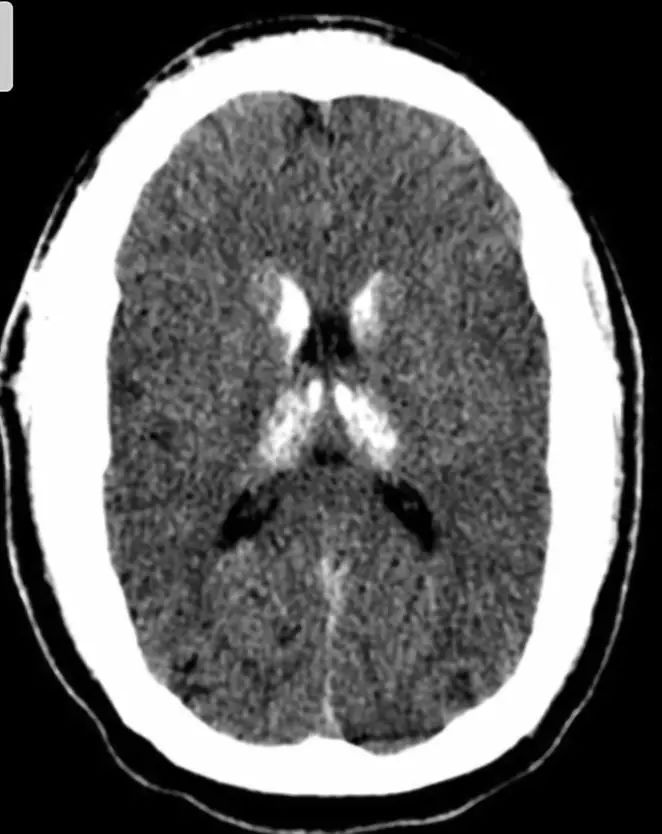

2. 结节性硬化

结节性硬化临床表现以皮脂腺瘤、癫痫和智力低下三联症为特征。病理特点为错构瘤,以室管膜下多发结节状钙化为主要特征性改变。